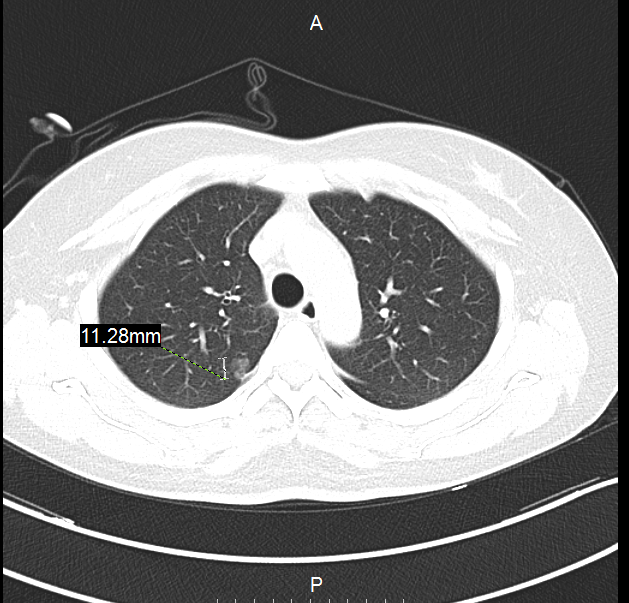

飞哥,40岁出头的年龄,在某省会城市务工,由于家里城市新开了个医院,有个亲戚在里面上班,新医院有个福利,体检半价,就去凑着省俩钱做了个体检,一查不要紧,发现了个肺部小结节,大约6mm,纯磨玻璃影。当时到未在意,大夫告诉他俩三月后再复查个胸部CT看看!等了三月查胸部CT发现结节增大,大约8mm,纯磨玻璃影,内似有血管征!医生告知他去省城医院看看吧!

慕名来我院,我们看到他的胸部CT后,告诉他“有早期肺癌可能,建议手术直接切除(因为病灶太小,不通过手术切除化验,无法确诊),术中快速病理确诊后决定手术切除方式(部分肺切除还是完整肺叶切除)”!患者听后连续摇头“不、不、不,不做,你们就吓唬我,骗我开刀!我啥症状都没有!”